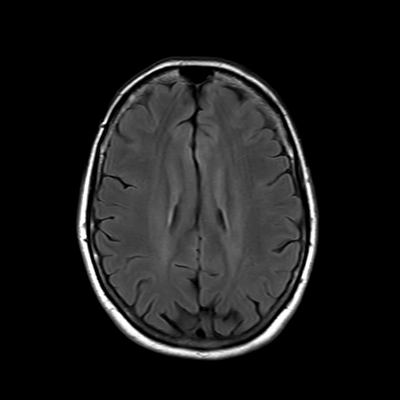

You also obtain an MRI of his brain once it's clinically safe to do so.

MRI brain (FLAIR)